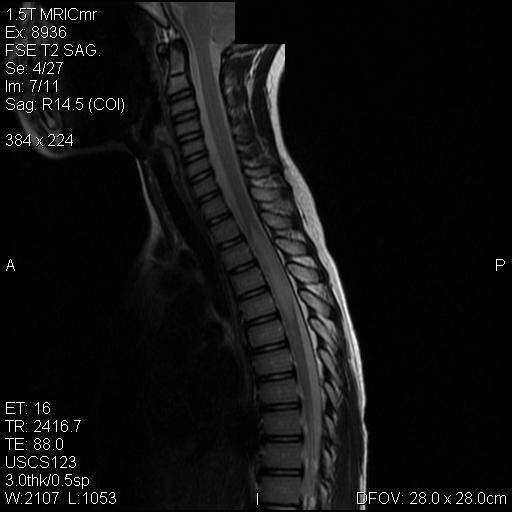

Representative images from the MR studies and specimen are illustrated below:

D. T2 |

Panel A to E are MR images. Panel F and G are taken from intraoperative cytologic preparation. Panel H to M are taken from frozen section. Panel N and O are from paraffin section. These sections are stained by hematoxylin-eosin stain. Panel P is immunohistochemistry for neurofilament proteins. Panel Q is stained by Luxol fast blue-Periodic acid Schiff (LFB-PAS) stain.

The segment of spinal cord at T3-T4 level is expanded and is accompanied by edema that runs from T2-T6. The expansion and edema is roughly symmetrical along the long axis of the cord. The expanded levels are isointense to the white matter of the spinal cord on T1-weighed images (Panel A). The edema is best demonstrated on T-weighed images (Panel B, C, and E). Patchy and poorly defined enhancement is demonstrated in the expanded areas (Panel D). The remaining levels of the spinal cord and the brain are free of abnormal changes.